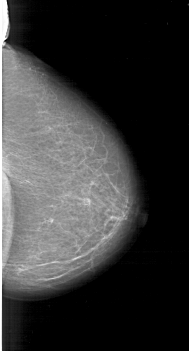

A_1207_1.RIGHT_CC

RIGHT_MLO LINES 6316 PIXELS_PER_LINE 3856 BITS_PER_PIXEL 12 RESOLUTION 43.5 NON_OVERLAY